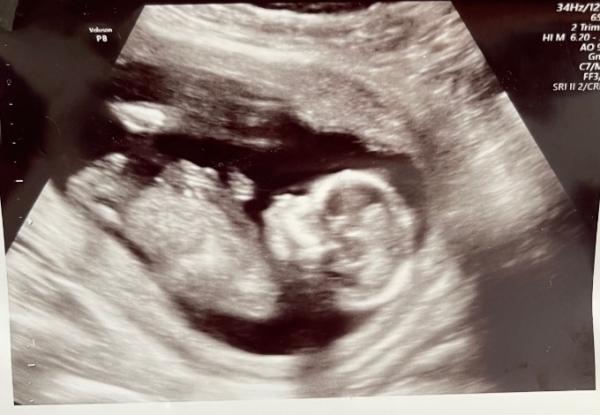

Hallöchen habt ihr schon mal von der Nub-Theorie gehört? Wenn ja wonach schaut für euch das Baby aus? Ssw 15+6

Ich kann keinen NUB erkennen

Das Baby liegt so, das man es gar nicht erkennen könnte...alles nur Spekulation, diese nub Theorie....

Wenn das Bild von jetzt ist, ist es für die Theorie eh schon zu spät :)